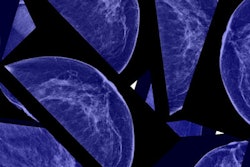

The Oslo Tomosynthesis Screening Trial was conducted between November 2010 and December 2012, and it included 24,301 women with 281 cancers; of these, 51 were interval cancers. The trial compared digital mammography's sensitivity and specificity with those of the following mammography screening combinations:

- DM versus DM + DBT

- DM versus DM + computer-aided detection (CAD)

- DM + DBT versus synthesized 2D mammography + DBT

Mammography screening sensitivity and specificity improved when DBT was added to both DM and DBT with synthesized 2D images, the group found. Adding CAD did not produce statistically significant differences.

| Performance metric | DM alone | DM + DBT | DM + CAD | Synthesized 2D + DBT |

| Sensitivity | 54.1% | 70.5% | 56.2% | 69% |

| Specificity | 94.2% | 95% | 94.2% | 95.4% |